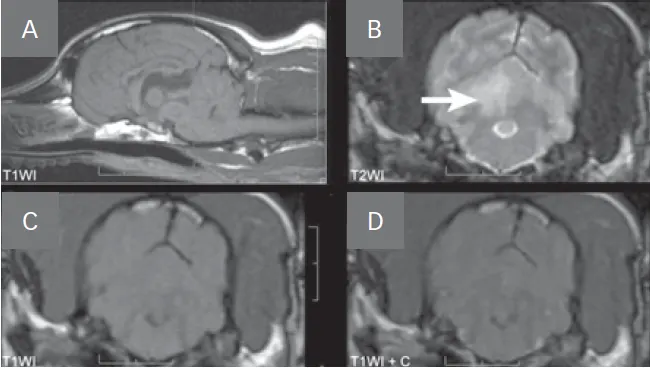

• The classic MRI characteristic of an ischemic stroke (Figure 1, see image gallery below) is an intra-axial lesion (often wedge-shaped) that is hyperintense (bright) on T2-weighted and fluid attenuation inversion recovery (FLAIR) images, iso- to hypointense (dark) on pre-contrast T1-weighted images, and minimal to no contrast enhancement.

FIGURE 1

MRI images of a dog with a right cerebellar infarct (A). Note the wedge-shaped intra-axial lesion in the right dorsal cerebellar gray matter (arrow) that is hyperintense on T2-weighted images (B), isointense on T1-weighted images (C), and does not contrast enhance (D).